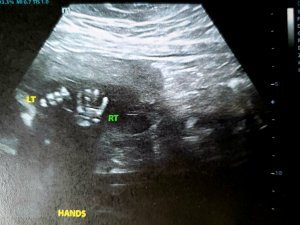

Since it’s now time for soup, Tylenol, and some more sleep, I’ll leave you with snapshots of my tenant’s spine, foot, and hands.

That is so cool Courtney!! Love the one showing the hands. So clear!! Hope you feel better!π